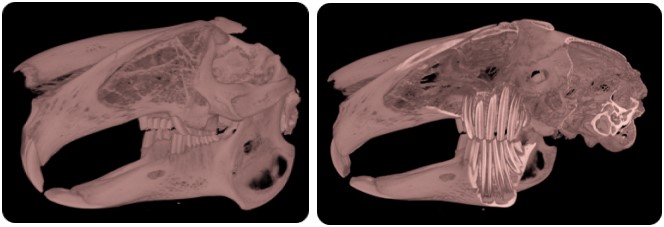

Range of CT only Applications: Rabbits

Range of CT only Applications: